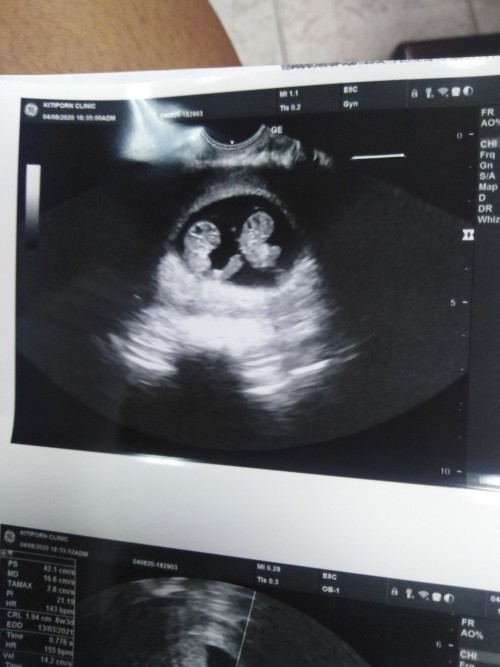

คนแรก ผช ครับ คนที่สองรอซาวด์เดือนหน้า💗